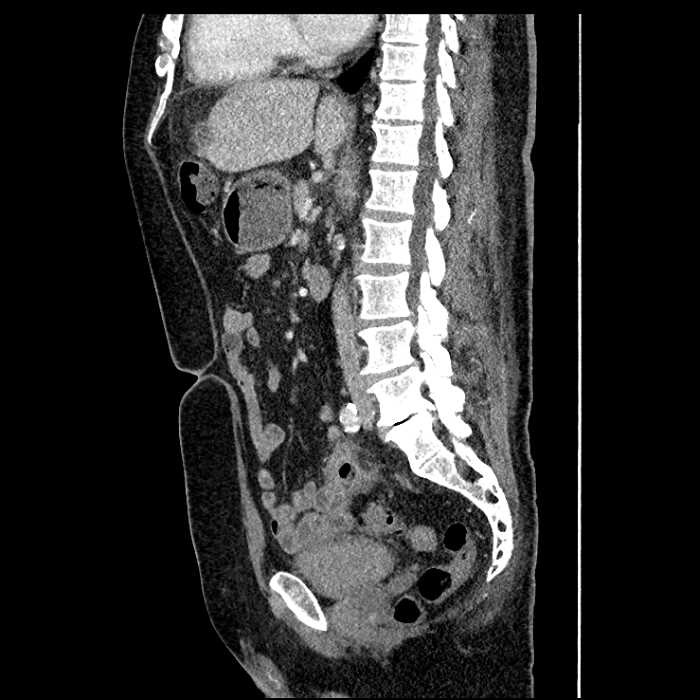

• Large fluid density structure in hepatic segments 7 and 8 measuring 10 x 7 x 7 cm with internal septation and circumferential ill-defined low density compatible with edema

• Peripherally enhancing subcapsular collections along the anterior margin of the left hepatic lobe measuring 3 x 1 cm and 2 x 1 cm

• Clearly marginated fluid density structure in segment 7 and several other scattered tiny hypodensities, which likely represent cysts

Acute sigmoid diverticulitis complicated by a small contained perforation and a large abscess in the right hepatic lobe. Additional small subcapsular abscesses along the anterior margin of the left hepatic lobe.

Additionally, loss of the normal fat plane between the peridiverticular collection and adjacent thickened loops of small bowel raises the potential for an enterocolonic fistula.

• The classic CT imaging appearance is a double target sign with internal low density surrounded by an internal enhancing rim (capsule) and a low density external rim (edema)

Hepatic abscess showing the double target sign with low density internally surrounded by a thin inner enhancing rim (red arrow) and ill-defined outer low density rim (yellow arrow). Blue arrow indicates an internal septation. Red arrows: additional smaller subcapsular abscesses. Red arrow: focal contained perforation associated with diverticulitis.